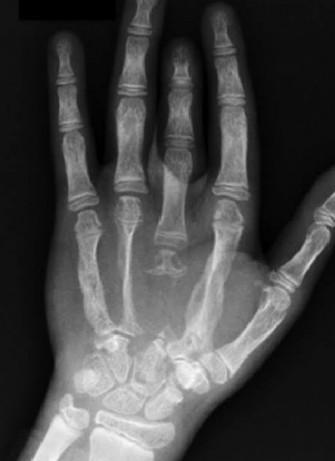

Le diagnostic est établi selon huit critères basés sur une radiographie d'aspect ostéolytique, la présence de tissus angiomateux et l'exclusion de toutes autres étiologies (infectieuses, héréditaire, cancéreuse). Cette pathologie évoque, dans un premier temps, une ostéoporose parcellaire.